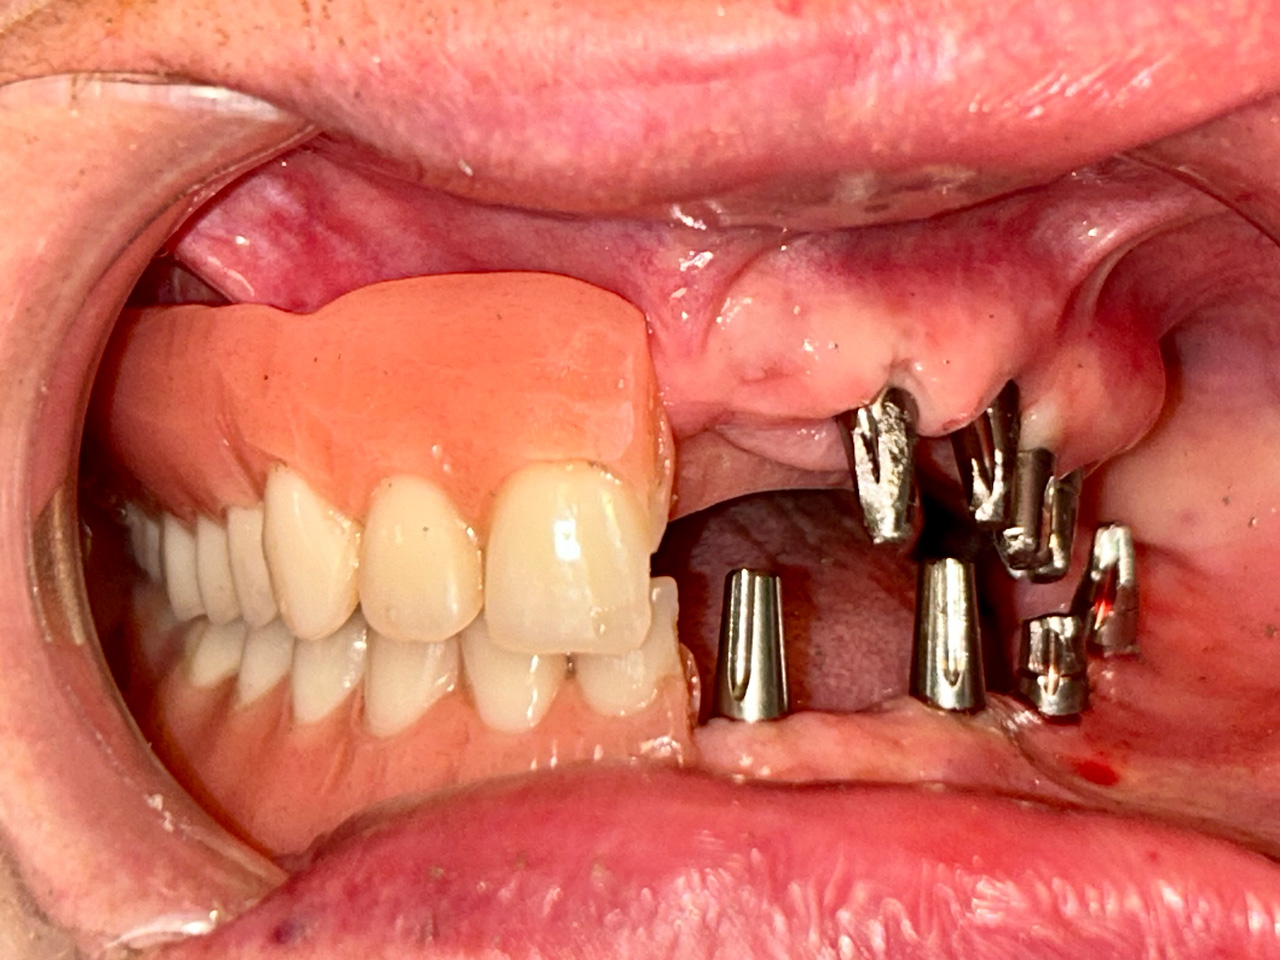

Teljes fogatlanság helyreállítása 2 nap alatt

Teljes fogatlanság helyreállítása 2 nap alatt azonnal terhelhető svájci IHDE implantátumokkal és PMMA műanyag hidakkal. Intraorális szkennerrel vettünk lenyomatot az implantáció után, és erre a digitális mintára készítette el a fogtechnika a hidak digitális tervezését, majd faragta ki műanyagból. Ezt a gyors munkát az azonnal terhelhető implantátumok és a digitális lenyomat, tervezés segítségével tudtuk megcsinálni mindössze 2 nap alatt. Dr. Kelemen Péter és a Symbion Fogtechnika munkája.